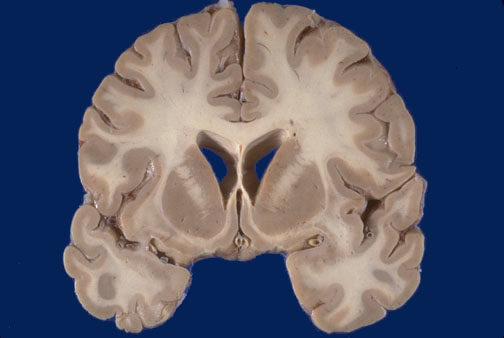

Identify the following regions of the normal brain by clicking in the image below:

Corpus callosum - Caudate (head) - Putamen - Septum pellucidum